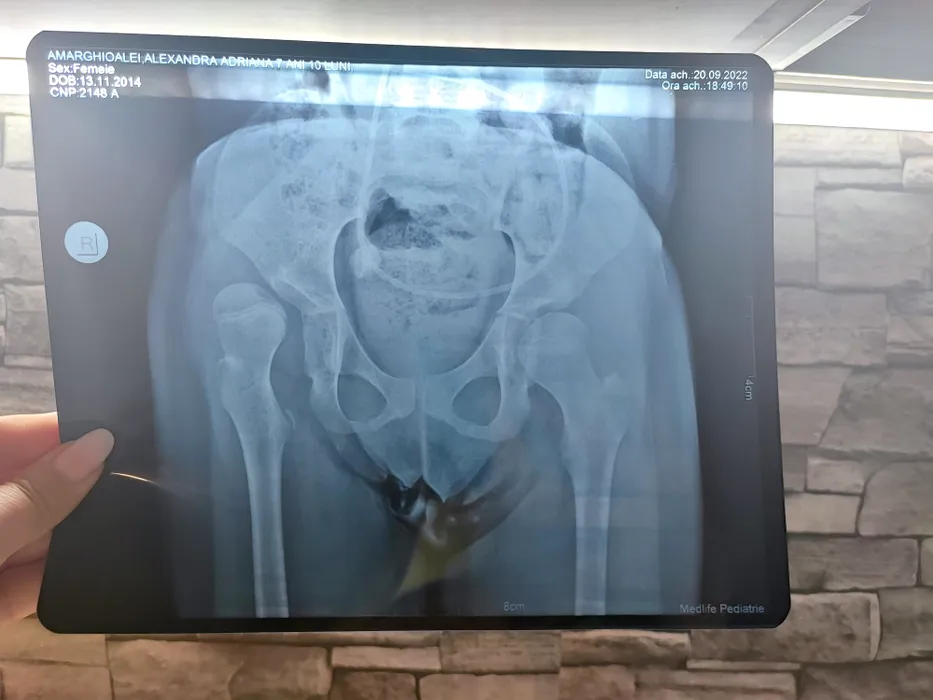

Strigăt de ajutor pentru Alexandra. De 7 ani face terapii zilnic, nu se poate bucura de viață ca alt copil de vârsta ei